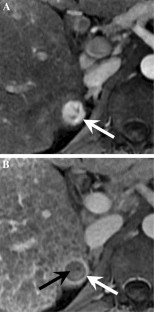

Fig. 2